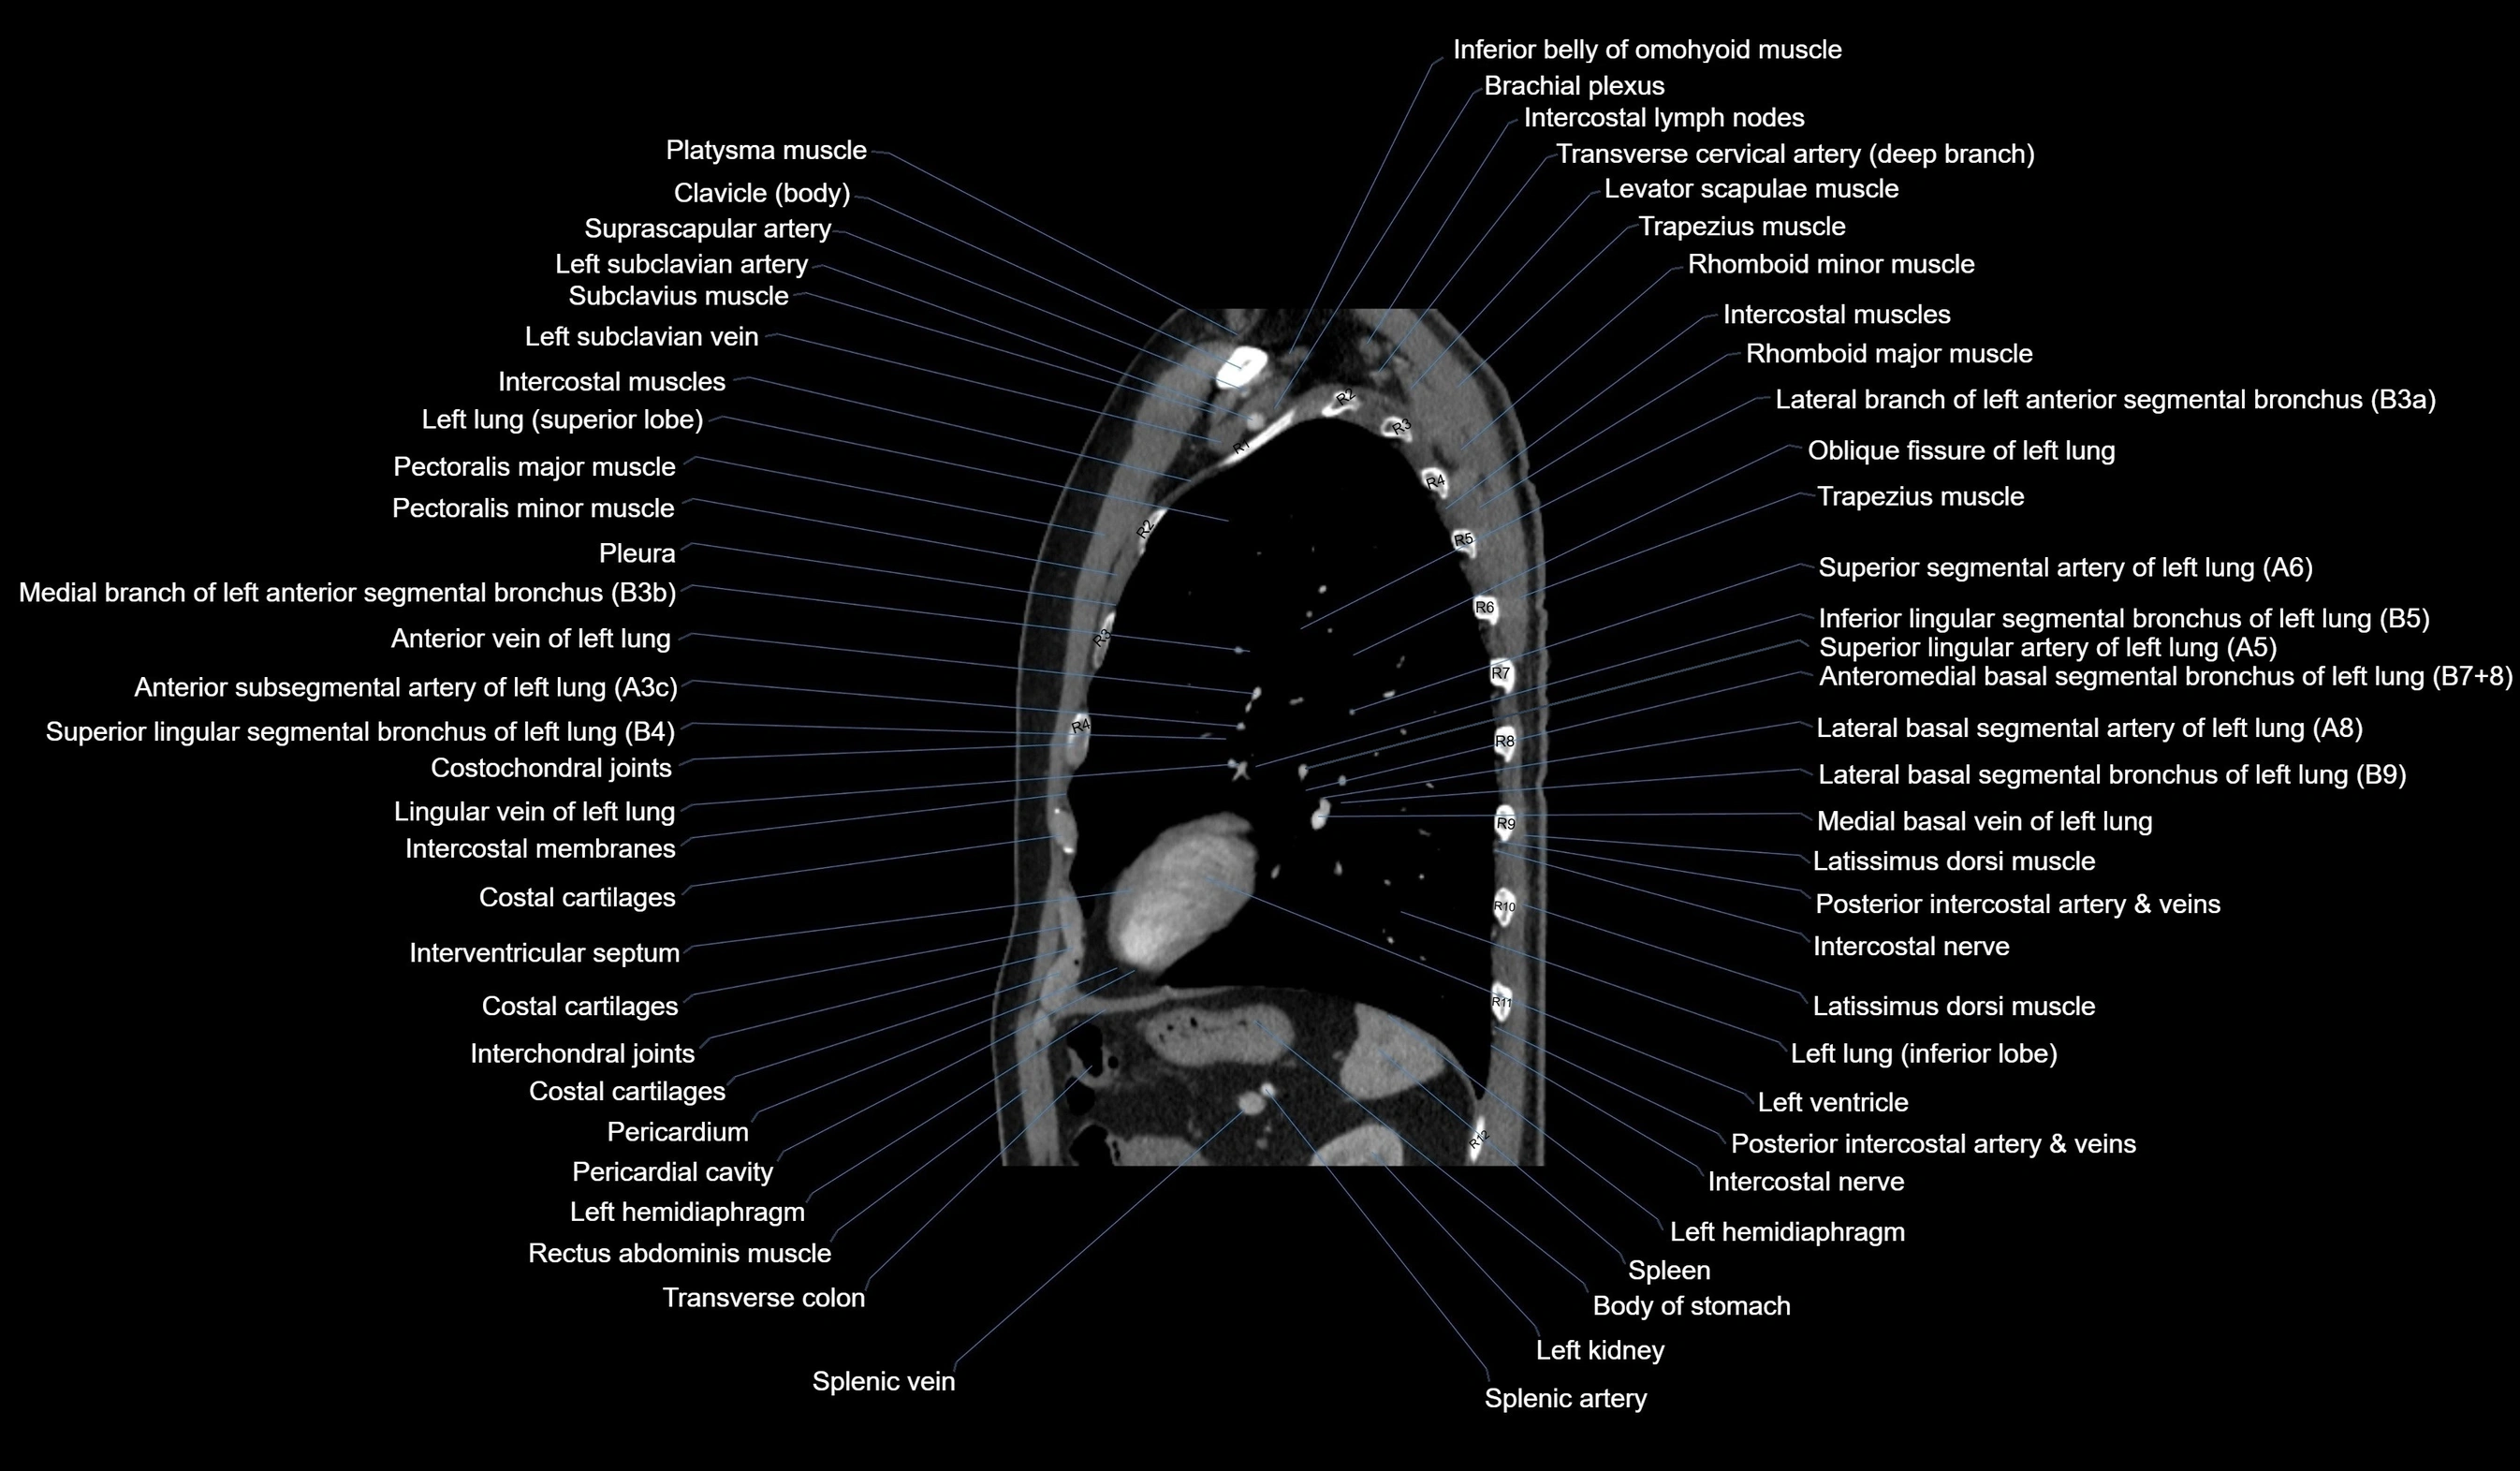

CT images